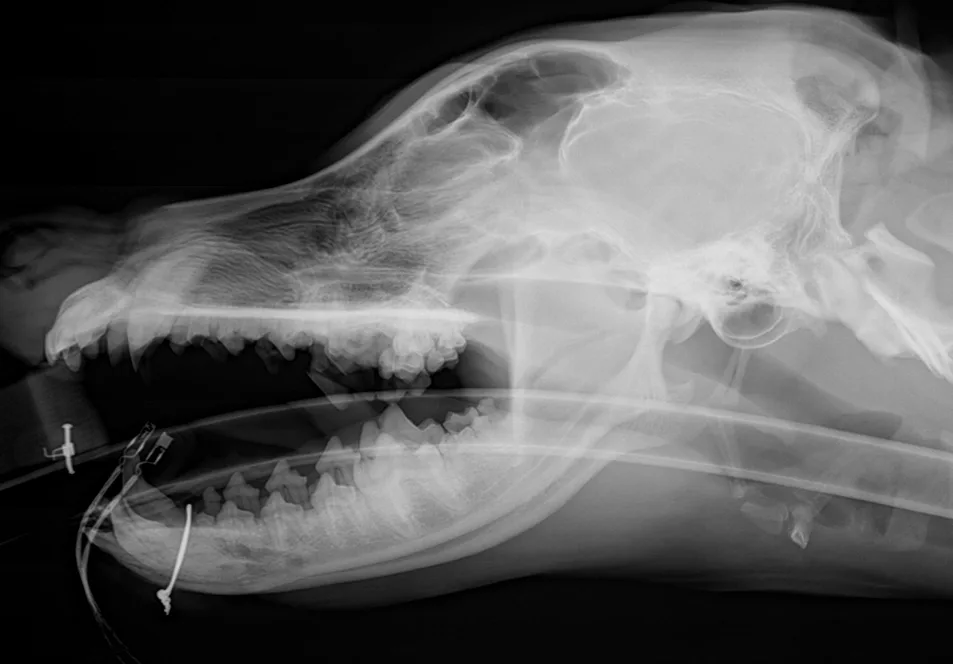

FIGURE 3A

Lateral radiographs of a caudal mandibular body fracture (A) and placement of 2 interfragmentary wires (B) in a dog

When managing fractures of the mandibular body, the surgeon’s goal is to provide stability to achieve bone union, whereas the dentist’s goal is to maintain tooth viability and proper occlusion. For example, a surgeon may want to place cerclage wires near the tooth root in the ventral mandible to secure good-quality bone at the tension surface, whereas a dentist might prefer an intraoral technique to preserve the root and relinquish a biomechanically superior location for implant placement. With proper planning, these goals can be balanced with a variety of methods. Interfragmentary wiring can be performed by placing 24- to 18-gauge wire throughout the length of the mandibular body; typically, >1 wire should be placed perpendicular to the fracture line for stability (Figure 3). Simple straight-line fracture configurations are best for this technique. In cases involving comminution of the mandible, plates or external fixators can be useful (Figures 4 and 5). These are typically placed on the lateral aspect of the mandible with careful avoidance of the tooth roots.